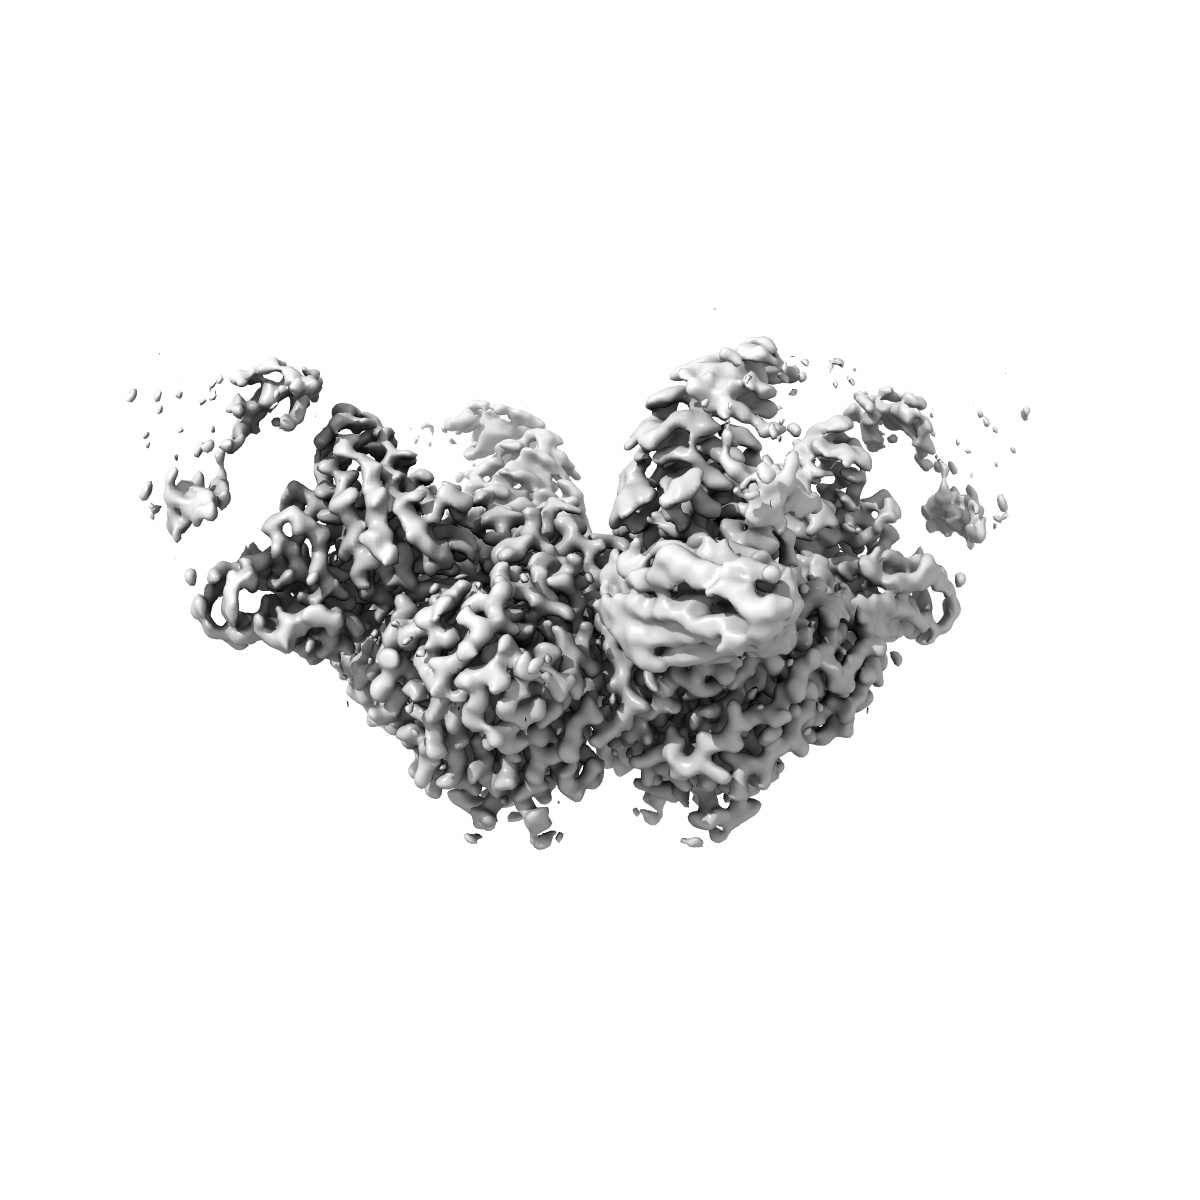

Cryo-EM structure of CR12044 Fab in complex with influenza virus neuraminidase from A/California/07/2009 (H1N1)

Single-particle2.53 Å

Sample: Cryo-EM structure of CR12044 Fab in complex with influenza virus neuraminidase from A/California/07/2009 (H1N1)